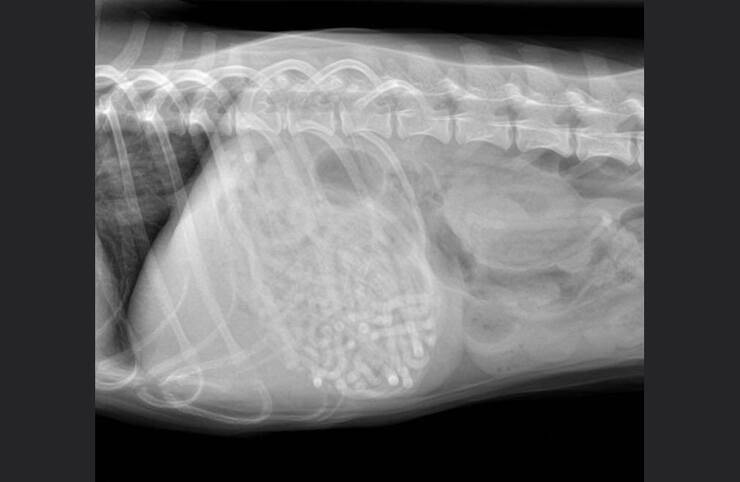

Qui il responso delle lastre ha lasciato tutti di sasso soprattutto per l’eccessiva quantità del corpo estraneo presente nello stomaco del cucciolo.

Dalle radiografie fatte dal veterinario si è scoperto che nel suo stomaco e all’interno del intestino tenue fosse presente una elevata quantità di elastici per capelli. Il piccolo Noodles, questo il nome del tenero quattro zampe, è stato operato d’urgenza, dove durante l’intervento i chirurghi hanno estratto dal suo stremato corpo un groviglio di elastici per capelli, molti di più rispetto a quelli che si potevano intravedere dalle radiografie.